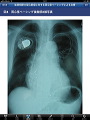

多種多様な心不全の症例について、国内随一の症例経験をもつ国立循環器病センターの50症例を収録。

症例名のほか、心電図/X線写真/エコー・CT・MRI等の画像から、各症例データを閲覧できます。